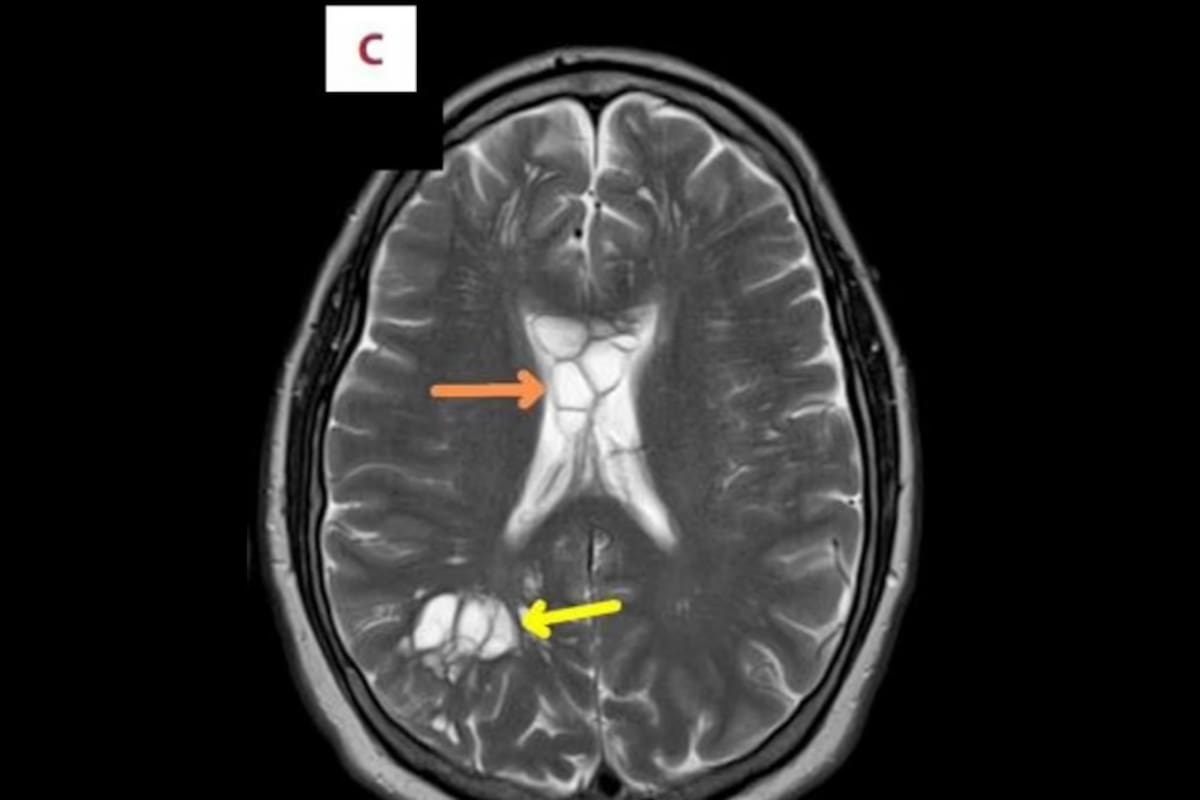

Orlando, Florida.- Un hombre acudió al médico después de padecer migrañas constantes en los últimos meses y que sus medicamentos dejaran de funcionar. Tras varios estudios, las exploraciones revelaron múltiples quistes en ambos hemisferios de su cerebro.

El personal médico confirmó que lo anterior era resultado de una tenia de cerdo que habitaba en su cerebro e irritaba el tejido de su cráneo. El paciente fue diagnosticado con la infección parasitaria neurocisticercosis.